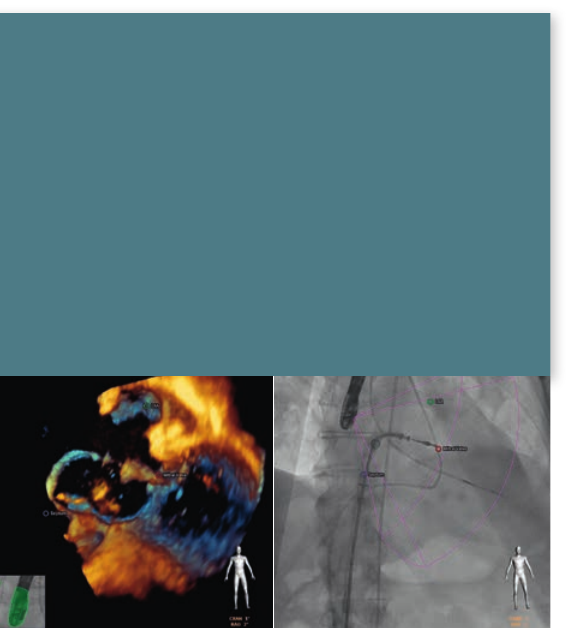

EchoNavigator

Increasingnumbersofpatientswithstructuralheart

disease(SHD)canbetreatedwithcatheter-based

techniques.Oneofthemainchallengesisvisualization;

Live3Dtransesophagealechocardiography(TEE)imaging

providescriticalinsightsintosofttissueanatomy,and

functionandowinformation.Atthesametime,X-rayis

invaluableforvisualizingdevices.Bothimages,however,

arerepresentedseparatelyinadifferentorientationand

sovaluabletimeisspentmentallyaligningthem.

Intuitively combining live X-ray and echo

guidance for Structural Heart Disease repair

Key benets

•Intuitivelycombineslive3DTEEechocardiographyand

uoroscopicimages.BringsTEEechocardiographyand

uoroscopicimagestogether,inreal-time.

•Understandwhereyouareinthe3Dspacemorequickly.

•AnatomicallandmarksinEchoareoverlaidonX-rayfor

guidanceofdevices.

•Directlycontrollableattableside,whichfacilitates

communicationwiththeechooperator.

•Promotesteamworkwithintheheartteaminthelab.

EchoNavigatortacklesthisissuehead-onbyintuitively

bringinglive3DTEEanduoroscopicimagestogether,

inreal-time,foraquickunderstandingofthe3Dspace.

Imagesfrombothmodalitiesareautomaticallyaligned

bytrackingtheTEEtransducerpositionandorientation

intheX-rayimage.Asaresult,relevantsofttissueanatomy

canbyvisualizedintheX-ray.Markersplacedonthe

softtissuestructureswithintheechoimage,automatically

appearontheX-rayforcontextandguidance.Thisprovides

cleartargetsforcatheternavigation.Theinterventional

operatorcandirectlycontroltheEchoNavigatorattableside,

whichfacilitatescommunicationwiththeechooperator.

Allofthisisdesignedtosimplifynavigation,deviceplacement

andpromotescommunicationwithintheheartteamduring

structuralheartdiseaseprocedures.

Philips EPIQ 7 ultrasound system Live 3D TEE of appendage

• Live3Dtransesophagealechocardiographyallowstheviewing

ofmitralvalves,aorticvalves,interatrialseptum,theleftatrial

appendageandallchambersoftheheartwithuniqueperspectives.

• PhilipsLive3DTEEprovidesreal-time3DandlivexPlaneviews.

Thesetoolsprovidemanybeating-heartviewsthatwerepreviously

seenonlyduringcardiacsurgery.

• Live3DTEEfeaturesprominentlyinrecentprofessionalsociety

recommendationsregardingechocardiographyintrans-catheter

interventions.(EAE/ASE*RecommendationsfortheUseof

EchocardiographyinNewTranscatheterInterventionsforValvular

HeartDisease.)

3Dzoomedappendageand

pulmonaryvein.